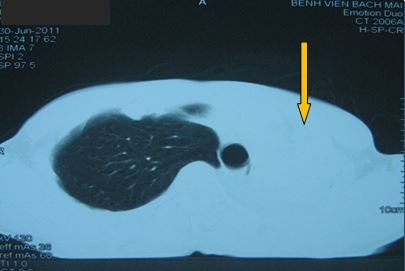

-          Bệnh nhân được tiến hành chụp cắt lớp vi tính ngực (CT ngực) đánh giá: có hình ảnh tổn thương toàn bộ thùy trên phổi trái

Hình ảnh tổn thương tái phát tương ứng với thùy trên phổi trái

Trước điều trị

Tổn thương ở vị trí thuỳ trên phổi trái: khối đông đặc và tổ chức u